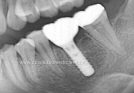

Clinical Cases

• Case1

• Case2

• Case3

• Case4

• Case5

• Case6

• Case7

• Case8

• Case9

• Case10